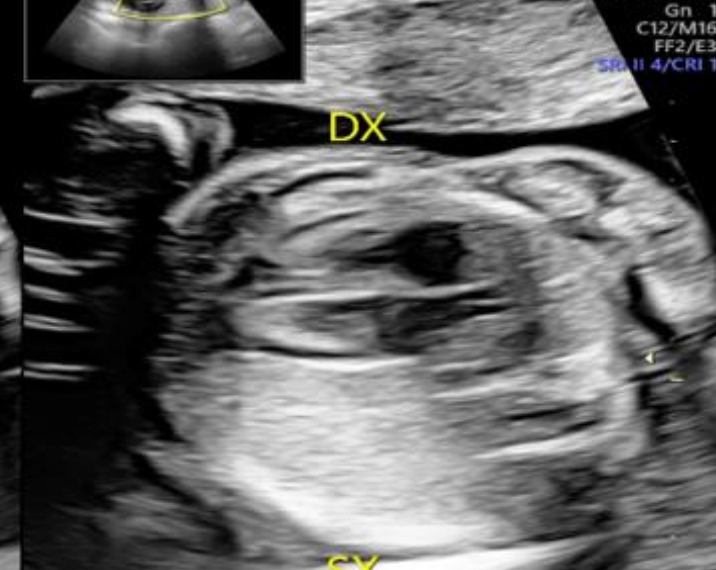

Guida al Counselling di Dicembre 2024: sequestro polmonare

vi presentiamo la guida al counseling di Dicembre 2024 sul sequestro polmonare!!

Guida Counseling - sequestro polmonare